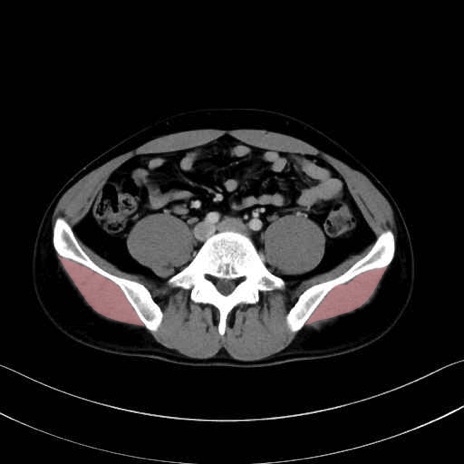

中殿筋 (Gluteus medius)